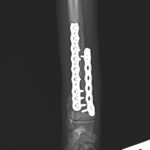

5ヶ月齢の小型犬がソファーからジャンプしたのちに橈骨骨折をしたとの事で、かかりつけ医より紹介受診されました。橈骨は遠位で階段状斜骨折を呈していました。遠位3穴にデザインされたストレートの1.5 Locking Plateをメインとし、橈骨の内側面からOrthogonal Plateにより骨接合術を行いました。しばらくは安静が必要です。